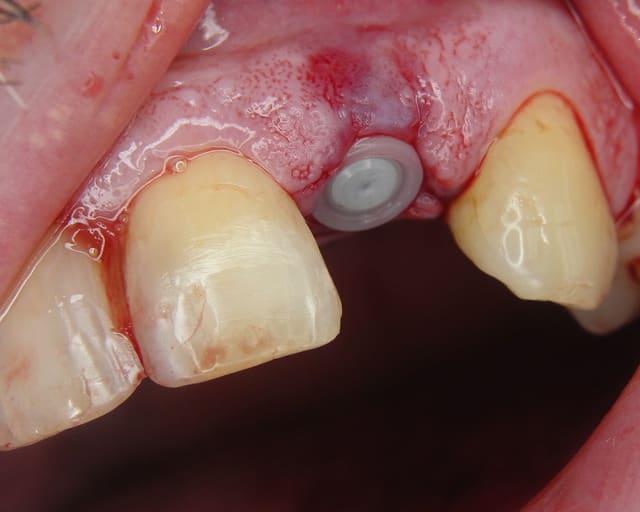

J'utilise la zircone depuis 7-8 ans,et je trouve que oui, la gencive est belle autour.

Par contre dans le dernier cas, je ne trouve pas que la gencive est belle, ell semble plutot inflammée...je crois que l'espace biologique n'est pas respecté.

Photo 2 du dernier cas, je crains beaucoup pour la plaque d'os en vestibulaire, même en flapless.

Plus sérieusement ,si la patiente avait eu un gummy smile alors je aurai rajouté de l´os. Mais ca fonctionne comme ca (en flapless + condensation )dans le temps. Je vais regarder pour retrouver la radio contrôle du cas.

Pour la paroie osseuse en vestibulaire de l'implant, le fait qu'il y ai ou pas un gummy smile me change pas grand chose, l'os est selon moi trop mince pour être stable dans le temps.

Oui sans condenser juste en flapless ca serai moins évident. Pour moi-même en condensant j´ai besoin de 1 mm buccal minimum(plus il y a mieux c´est) mais dans ma pratique et celles mes confrères ca fonctionne et cela dure dans le temps depuis 16 ans.

En dessous il y a des photos, dans une on voit (troisième) qu il n y a pas de resorption de l´os après 14 ans, ce que l´on voit c´est l´os très fin condensé sur l´implant.